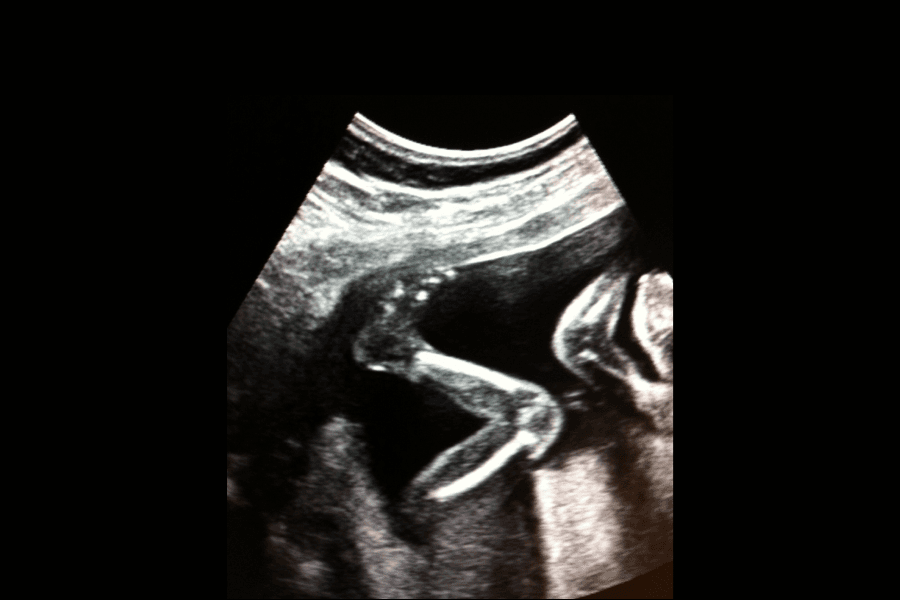

Dieser besondere Moment, wenn du in der zweiten Hälfte der Schwangerschaft dein kleines Wunder zum ersten Mal spürst, wird oft als Quickening bezeichnet. Es kann sich wie ein zartes Kitzeln, kleine Bläschen oder sanfte Wellen anfühlen – und wird anfangs oft mit Luft im Bauch oder Muskelzuckungen verwechselt.

Wenn du dein erstes Kind erwartest, spüren die meisten Frauen die Bewegungen zwischen der 18. und 20. Schwangerschaftswoche. Mamas, die schon einmal geboren haben, können sie manchmal sogar einen Monat früher wahrnehmen – etwa ab der 16. Woche. Das Spüren der ersten Kindsbewegungen ist sehr individuell und kann bei manchen Frauen auch später als in der 20. Woche auftreten. Ab der 25. Schwangerschaftswoche solltest du dein Baby jedoch jeden Tag spüren können. Die Lage der Plazenta kann beeinflussen, wann du die Bewegungen bemerkst – eine Vorderwandplazenta kann das Spüren zum Beispiel verzögern, aber sie schwächt die Bewegungen nicht – du spürst sie einfach nur etwas später.